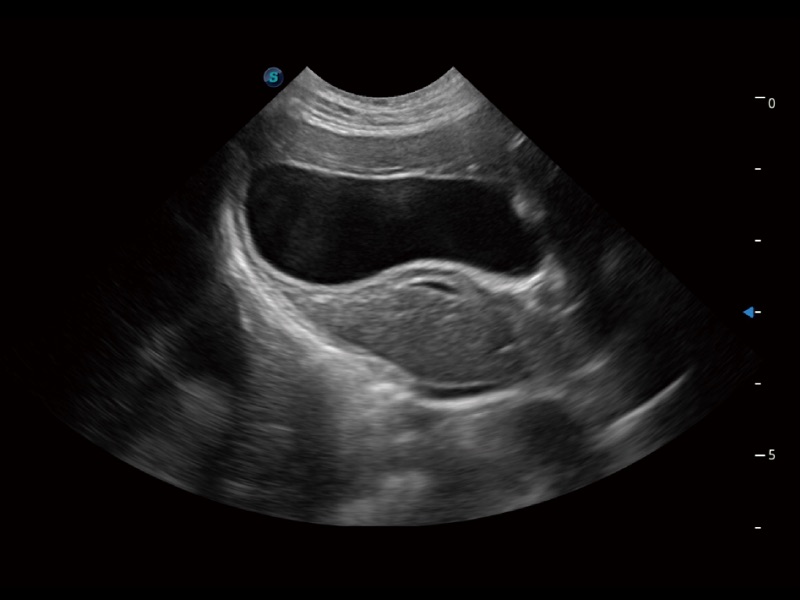

為精細(xì)結(jié)構(gòu)及組織邊緣提供高清晰度的圖像和更大的成像視野。幫助減輕醫(yī)生的用眼疲勞,快速精準(zhǔn)獲得測(cè)量的數(shù)據(jù)。